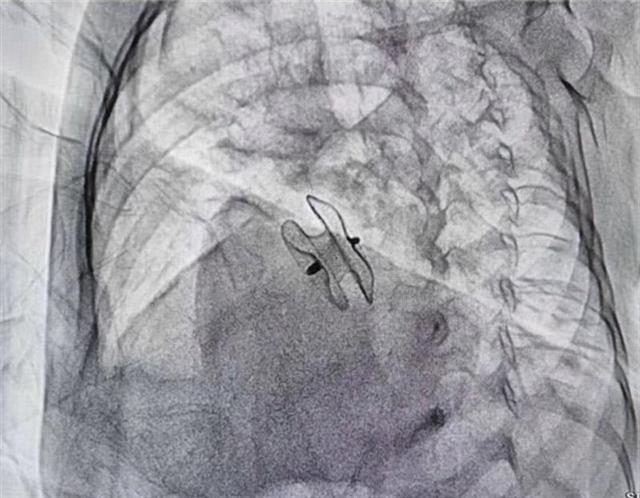

通过介入手术在心内撑开一把“小伞”修补缺口

“小伞”撑开挡住2岁女童心缺口

“孩子实在是不能等了,我只能试一试。”7月20日,李翔带着女儿小梦到武汉儿童医院来求诊。得知小梦家庭贫困,武汉儿童医院将她纳为“爱佑童心”爱心项目的资助对象,该院心血管内科主任张勇通过微创介入方式,在小梦心内撑开一把“小伞”,成功将缺损牢牢堵住,7月25日小梦康复出院。